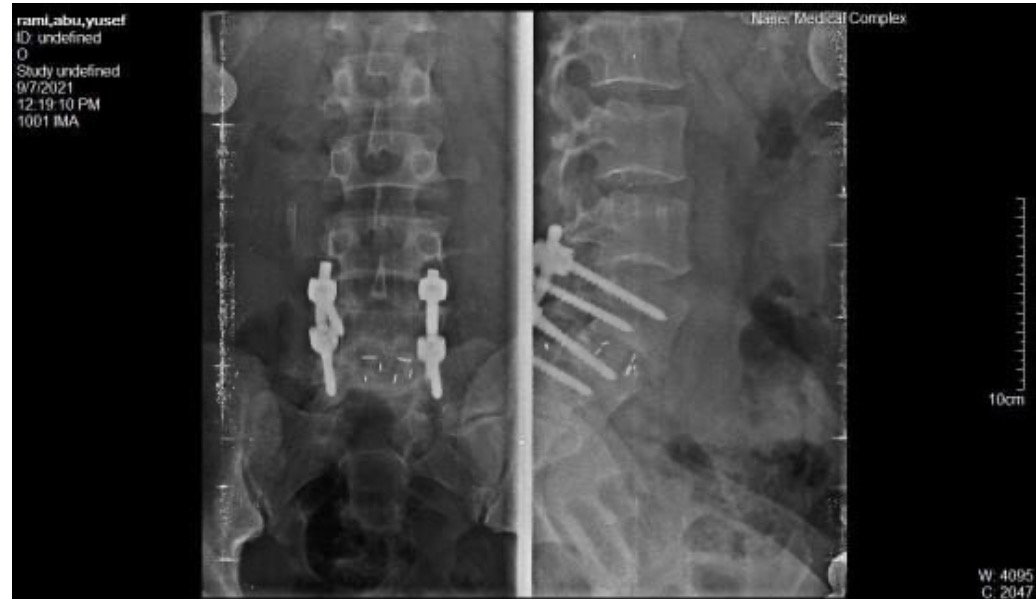

Rami has a debilitating spinal injury he is in urgent need of surgery for, but this has obviously been impossible with the ongoing genocide in Gaza. With this, he is unable to earn money and source food for his family who are now essentially starving.